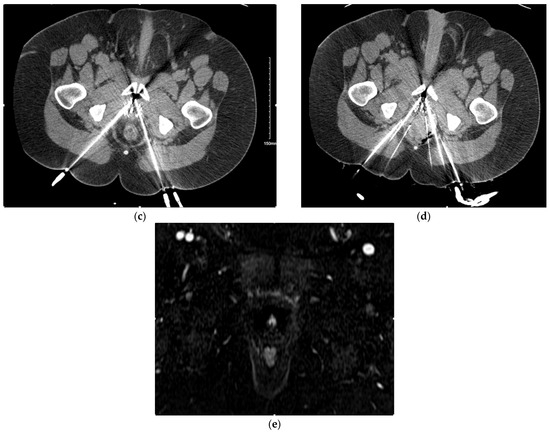

- Woodrum, D.A.; Kawashima, A.; Karnes, R.J.; Davis, B.J.; Frank, I.; Engen, D.E.; Gorny, K.R.; Felmlee, J.P.; Callstrom, M.R.; Mynderse, L.A. Magnetic resonance imaging-guided cryoablation of recurrent prostate cancer after radical prostatectomy: Initial single institution experience. Urology 2013, 82, 870–875. [Google Scholar] [CrossRef] [PubMed]

- Gangi, A.; Tsoumakidou, G.; Abdelli, O.; Buy, X.; de Mathelin, M.; Jacqmin, D.; Lang, H. Percutaneous MR-guided cryoablation of prostate cancer: Initial experience. Eur. Radiol. 2012, 22, 1829–1835. [Google Scholar] [CrossRef] [PubMed]

- De Marini, P.; Cazzato, R.L.; Garnon, J.; Tricard, T.; Koch, G.; Tsoumakidou, G.; Ramamurthy, N.; Lang, H.; Gangi, A. Percutaneous MR-guided whole-gland prostate cancer cryoablation: Safety considerations and oncologic results in 30 consecutive patients. Br. J. Radiol. 2019, 92, 20180965. [Google Scholar] [CrossRef] [PubMed]

- Overduin, C.G.; Jenniskens, S.F.M.; Sedelaar, J.P.M.; Bomers, J.G.R.; Fütterer, J.J. Percutaneous MR-guided focal cryoablation for recurrent prostate cancer following radiation therapy: Retrospective analysis of iceball margins and outcomes. Eur. Radiol. 2017, 27, 4828–4836. [Google Scholar] [CrossRef]

- Bomers, J.G.; Yakar, D.; Overduin, C.G.; Sedelaar, J.P.; Vergunst, H.; Barentsz, J.O.; de Lange, F.; Fütterer, J.J. MR imaging-guided focal cryoablation in patients with recurrent prostate cancer. Radiology 2013, 268, 451–460. [Google Scholar] [CrossRef]